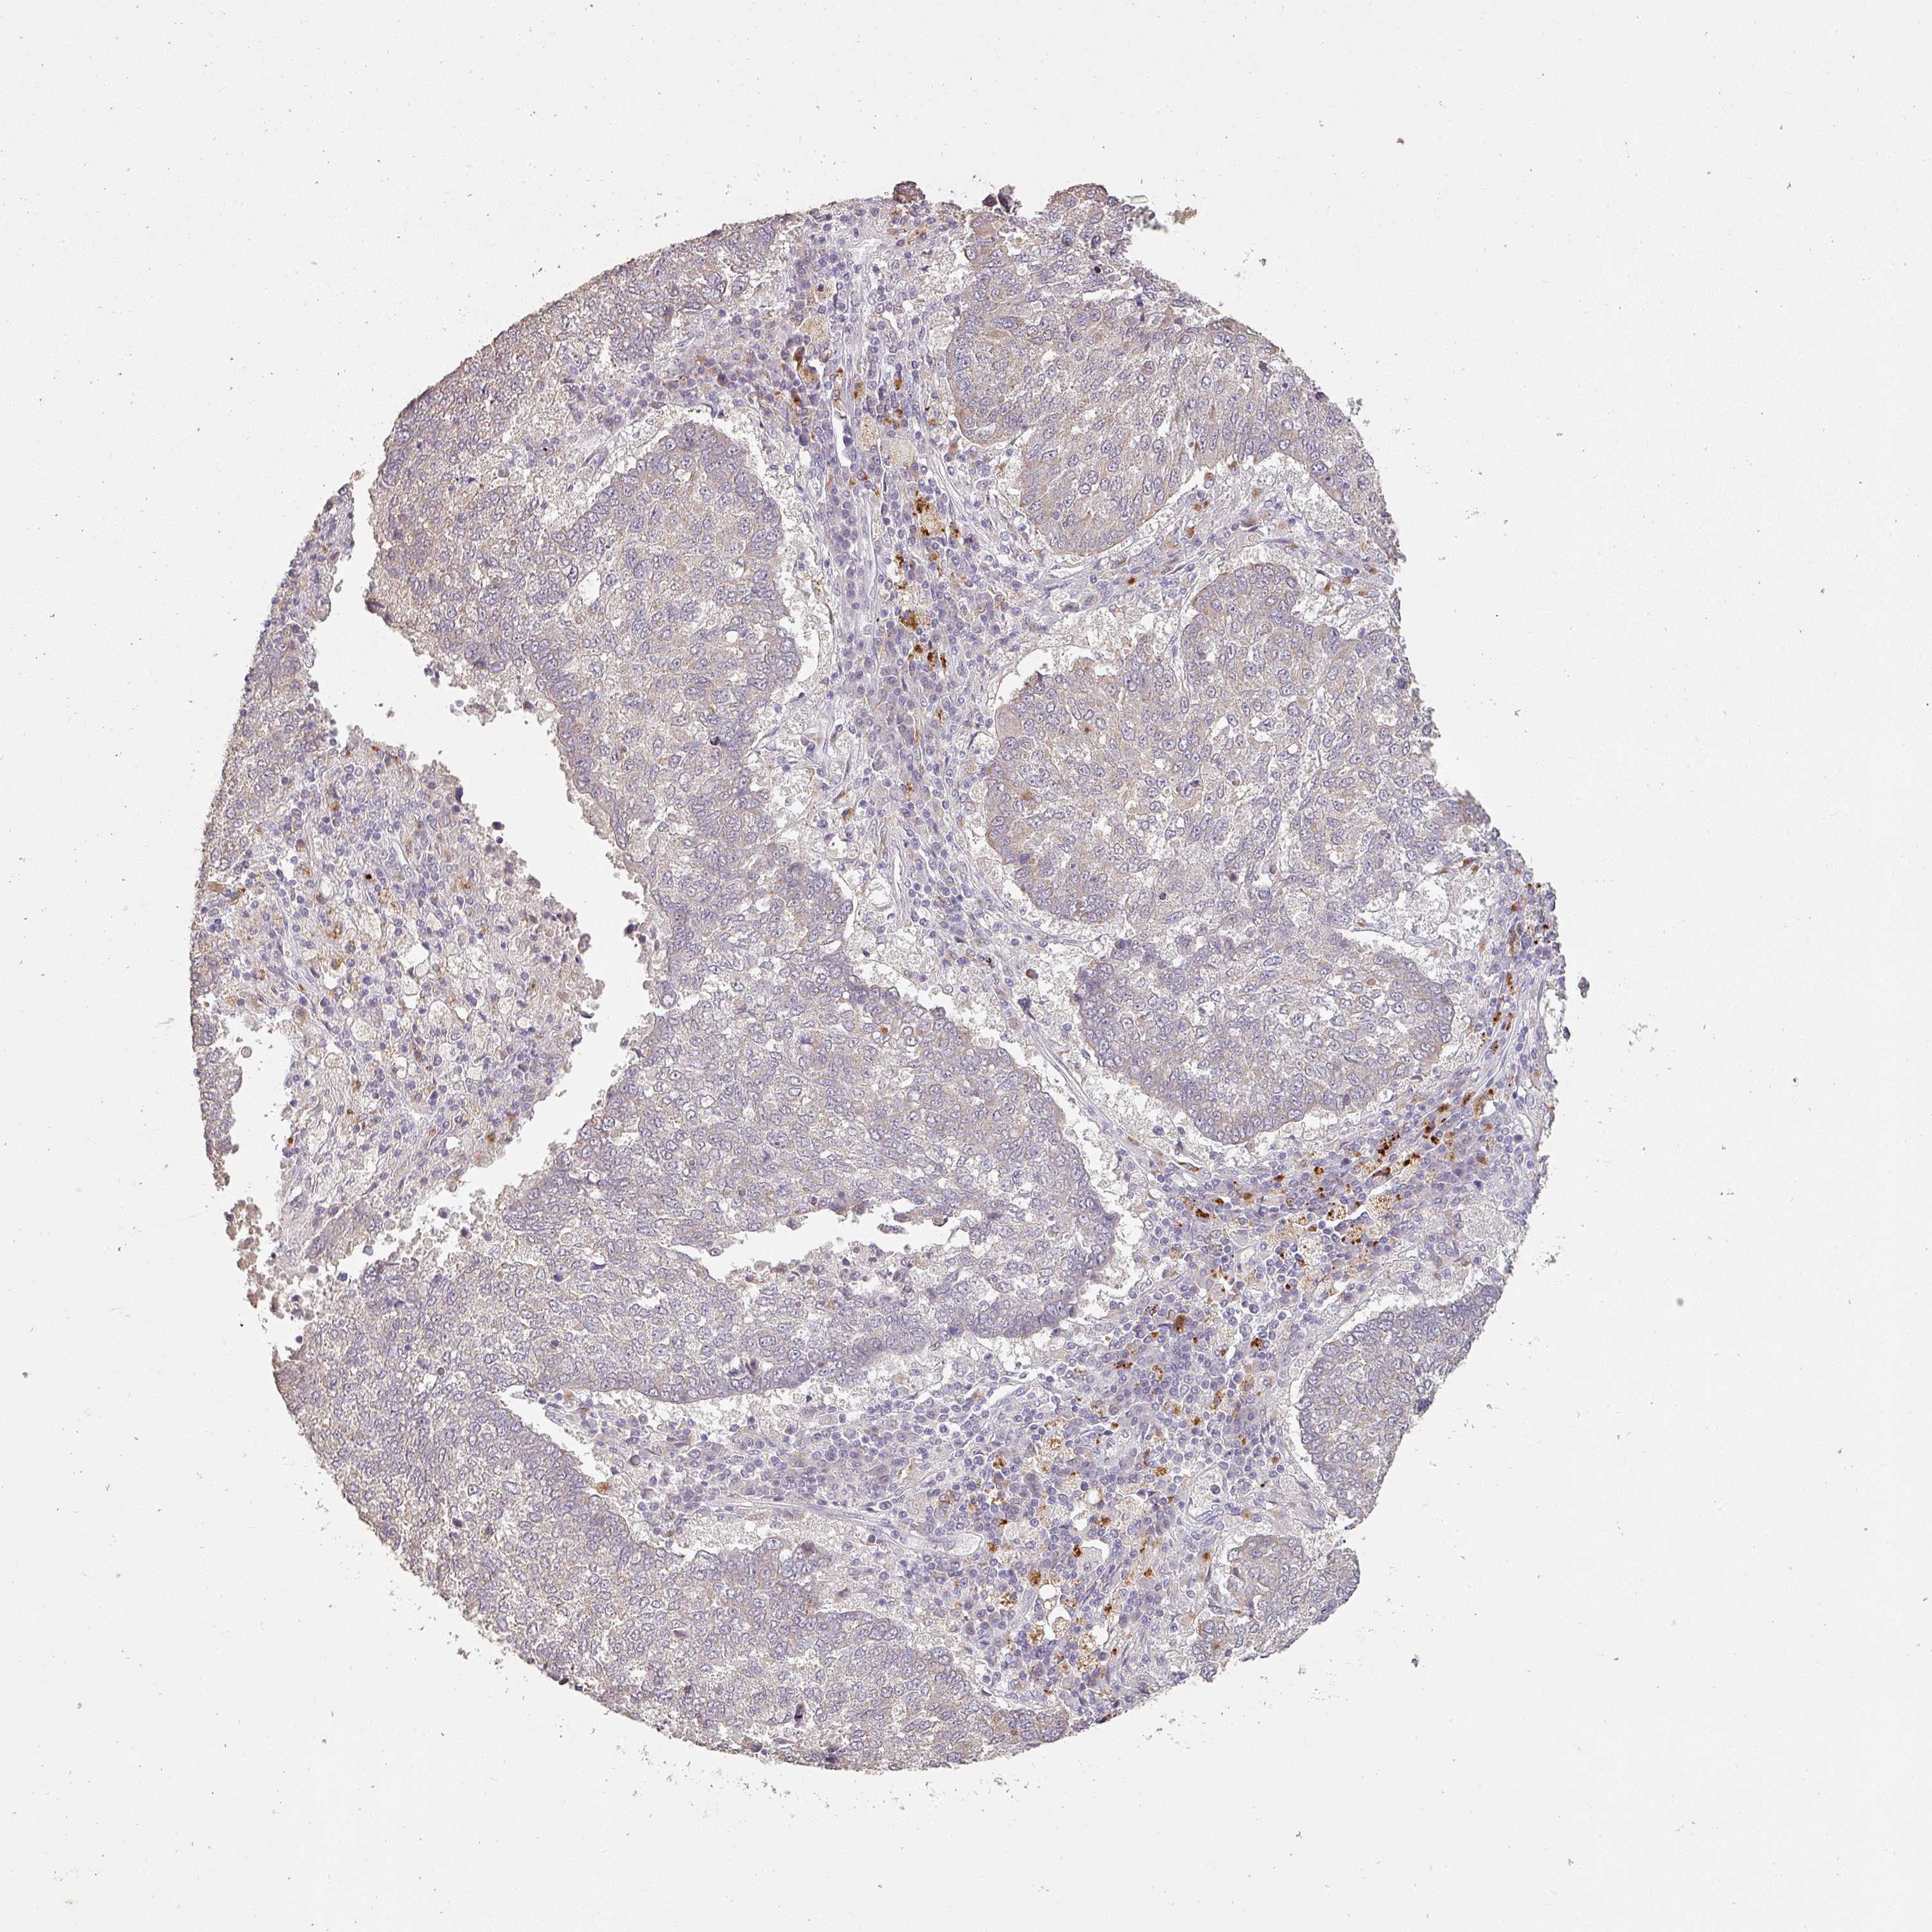

CANCER LUNG CANCER Show tissue menu

Lung cancer

Human cancer

Lung adenocarcinoma

Lung squamous cell carcinoma